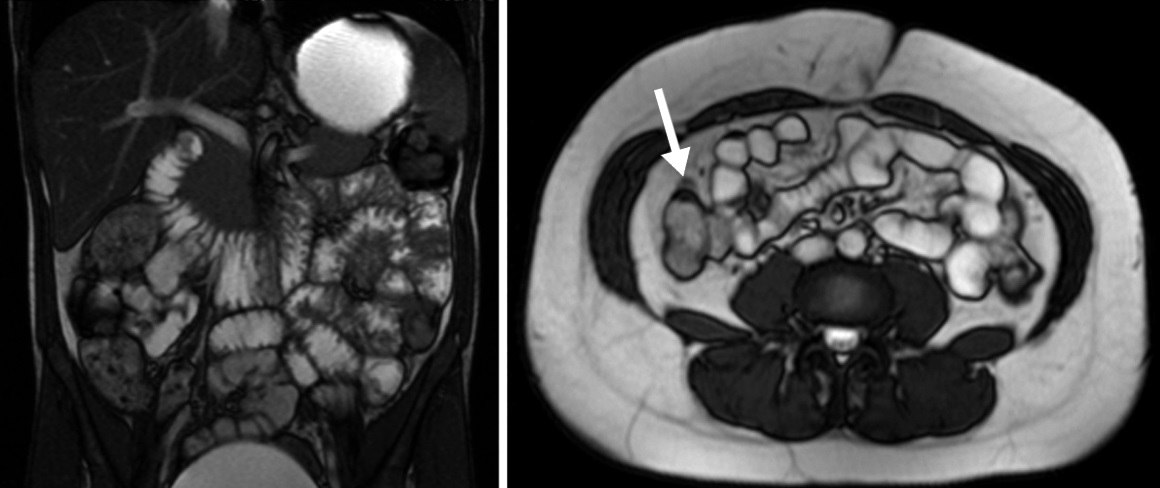

Figura 7

Misma paciente de la figura 6

a y b) Secuencia T2 axial con saturación grasa. Se observa un grupo de asas en fosa ilíaca derecha de paredes engrosadas en forma concéntrica y con edema submucoso (flecha).

c y d) Secuencia de difusión con valor b 800. E: Mapa de ADC. Se observa intensa restricción a la difusión del agua de las asas afectadas. En esta paciente en quien no se pudo realizar gadolinio debido a las semanas de gestación se muestra la importancia de la difusión en la valoración de actividad inflamatoria.